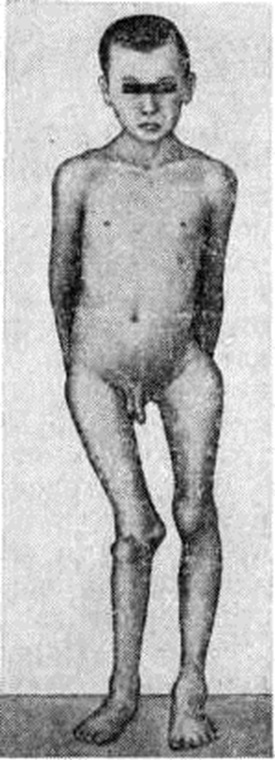

Отдельные кости подвергаются характерной деформации (рисунок 2). При локализации очага Фиброзная остеодисплазия в проксимальном конце бедра оно приобретает вид пастушьей палки с изгибом выпуклостью кнаружи, большой вертел поднимается вверх на уровень тела подвздошной кости; развивается варусная деформация бедра. Голени при их поражении изгибаются чаще кнаружи и кпереди. Плечевые кости булавовидно утолщаются в проксимальных отделах. Поражение костей таза сопровождается деформацией тазового кольца, позвонков, рёбер, грудной клетки. Поражение костей черепа и их деформация вызывают асимметрию и обезображивание лица, вторичные нарушения зрения и слуха, головные боли, экзофтальм (смотри полный свод знаний). Деформации костей усугубляются неправильно сросшимися патологический переломами. Почти постоянным симптомом Фиброзная остеодисплазия костей нижней конечности является хромота (смотри полный свод знаний), от лёгкого прихрамывания до выраженного нарушения походки. Функциональная неполноценность конечности сопровождается атрофией мягких тканей, вторичными деформациями суставов, позвоночника.

Полиоссальная форма Фиброзная остеодисплазия часто сочетается с патологический кожной пигментацией (пятна различной величины и формы всех оттенков коричневого цвета), ранним половым созреванием (смотри полный свод знаний), гипертиреозом (смотри полный свод знаний: Тиреотоксикоз). Костные изменения, пигментация кожи и преждевременное половое созревание у женщин — триада признаков, известных как синдром, или болезнь, Олбрайта (смотри полный свод знаний: Псевдогипопаратиреоз). Прогрессирование Фиброзная остеодисплазия заканчивается с половым созреванием.